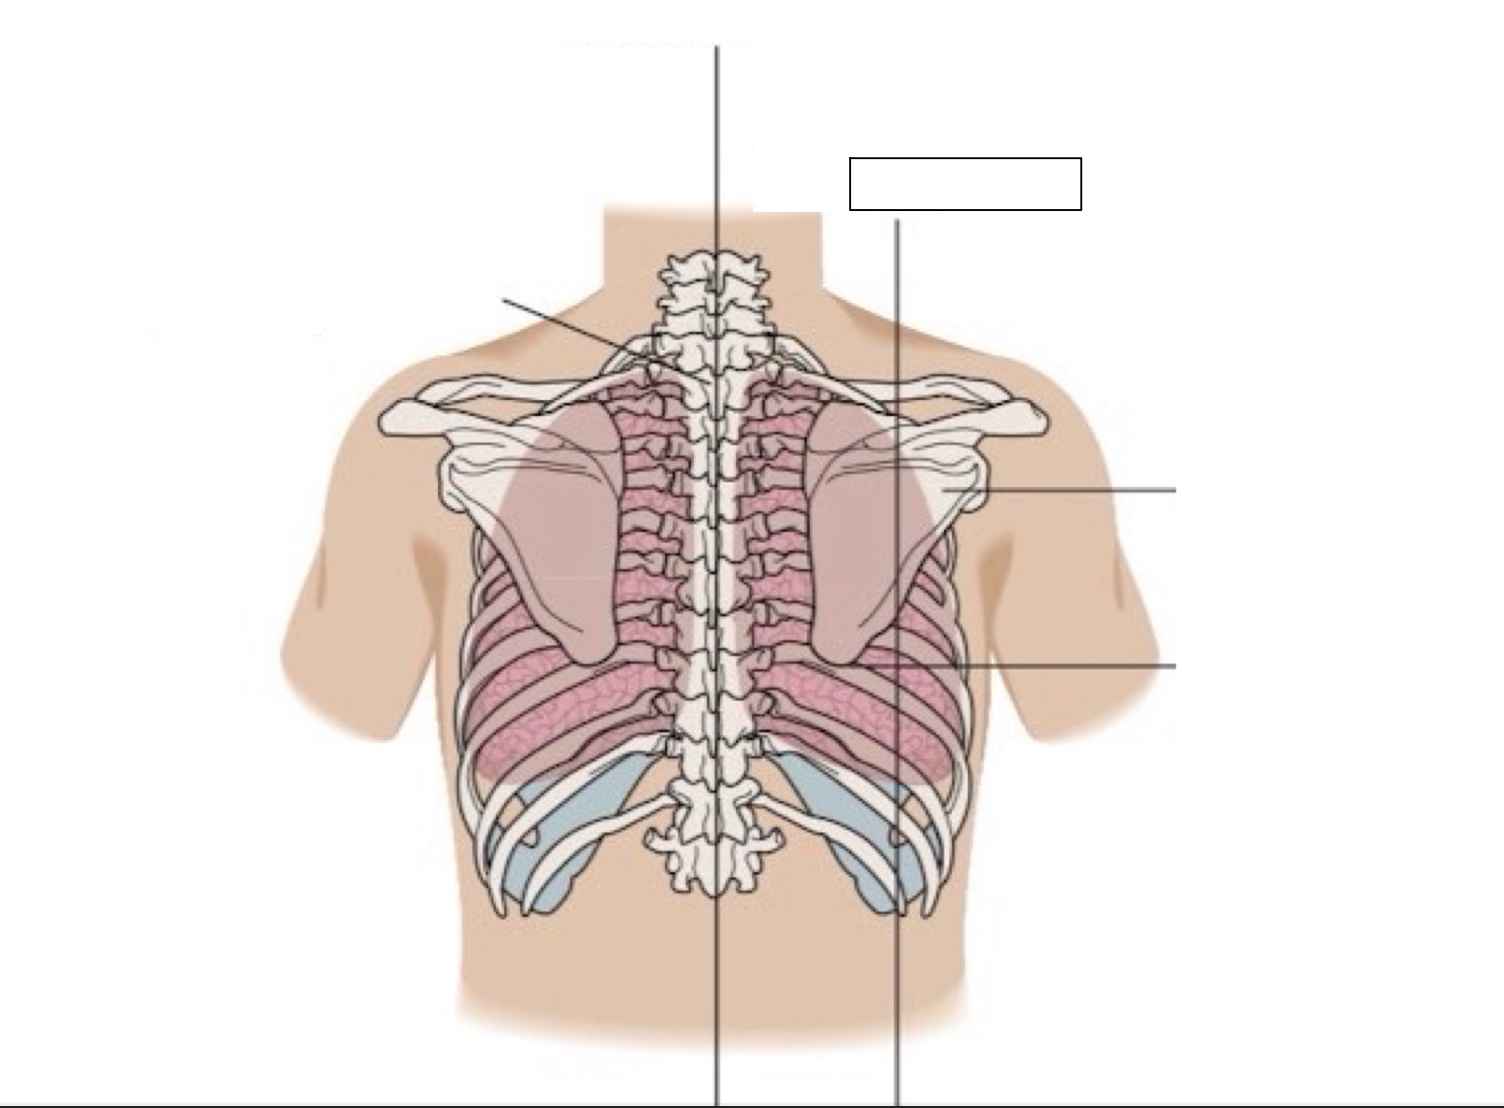

inferior angle of scapula

scapula

midscapular line

midspinal line

spinous process